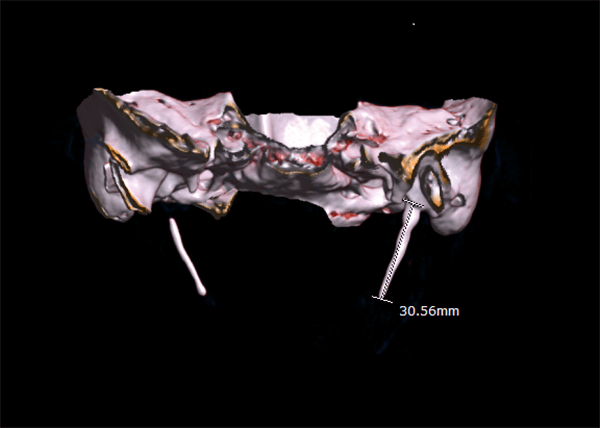

Eagle syndrome is a rare condition where the styloid process becomes elongated or the stylohyoid ligaments become calcified. When the process elongates, it can constrict nerves, the carotid artery, and create a variety of symptoms that are often misdiagnosed. (see Image 1 and 2)

Radiographic Imagery

Is the styloid process approximately 2.5cm, or has it elongated? How does the TMJ look? If the styloid process is elongated and the TMJ looks relatively normal, a referral to an ear, nose, and throat specialist (ENT) is advised.

The ideal radiologic review is with 3D computed tomography. However, many dental offices do not have this imagery available.4 The referral to an ENT for further examination should be recommended if a patient does not respond to TMD therapy, NSAIDs, or when radiographs do not reveal any significant temporal mandibular disorder (TMD) issues.